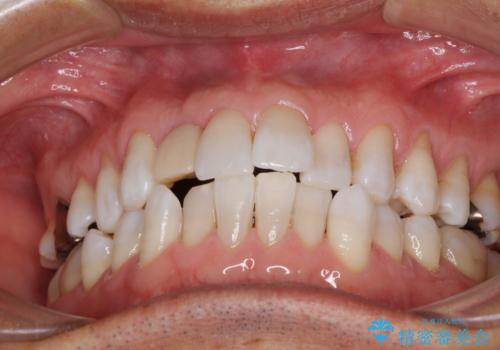

治療途中の前歯を治したい インビザライン矯正とオールセラミッククラウン

- 治療途中の前歯と上下前歯のデコボコ気にして来院された患者様です。

前歯のデコボコはインビザラインにより歯列を整え、その後に、前歯などをオーダーメイドタイプのオールセラミッククラウンにて補綴治療することとしました。